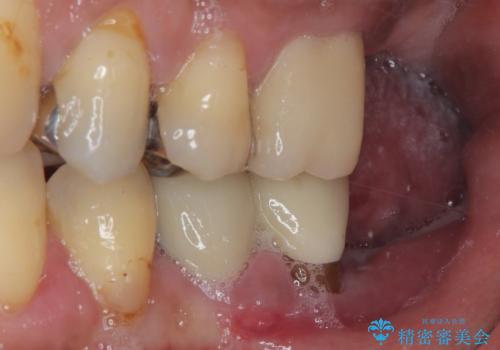

骨吸収が大きかったため、待機期間を必要としましたが、外科処置は初診時の抜歯も含めて3回に抑えることができ、半年の短期間で治療を終えることができました。